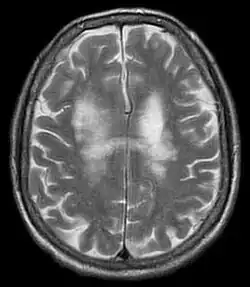

| T2-weighted MRI showing progressive multifocal leukoencephalopathy | |

PML is diagnosed in a patient with a progressive course of the disease, finding JC virus DNA in spinal fluid together with consistent white-matter lesions on brain magnetic resonance imaging (MRI); alternatively, a brain biopsy is diagnostic[1] when the typical histopathology of demyelination, bizarre astrocytes, and enlarged oligodendroglial nuclei are present, coupled with techniques showing the presence of JC virus.[12]

Characteristic evidence of PML on brain CT scan images are multifocal, noncontrast enhancing hypodense lesions without mass effect, but MRI is far more sensitive than CT.[12] The most common area of involvement is the cortical white matter of frontal and parieto occipital lobes, but lesions may occur anywhere in the brain, such as the basal ganglia, external capsule, and posterior cranial fossa structures such as the brain stem and cerebellum.[12] Although typically multifocal, natalizumab-associated PML is often monofocal, predominantly in the frontal lobe.[12]